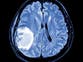

- Tumours can be either benign (non-cancerous) or malignant (cancerous), with benign tumours sometimes requiring treatment due to their location or effects.

- While solid cancers are malignant tumours, not all tumours are cancerous, and not all cancers, such as blood cancers like leukaemia, form solid masses.